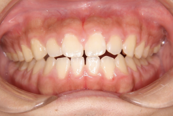

症例 ②

●空隙歯列を伴う開咬

●前歯を後ろに下げるために必要な隙間が存在している

- 治療後 -

▶︎隙間を閉じながら上下前歯を後ろに下げ、開咬の改善を行いました。